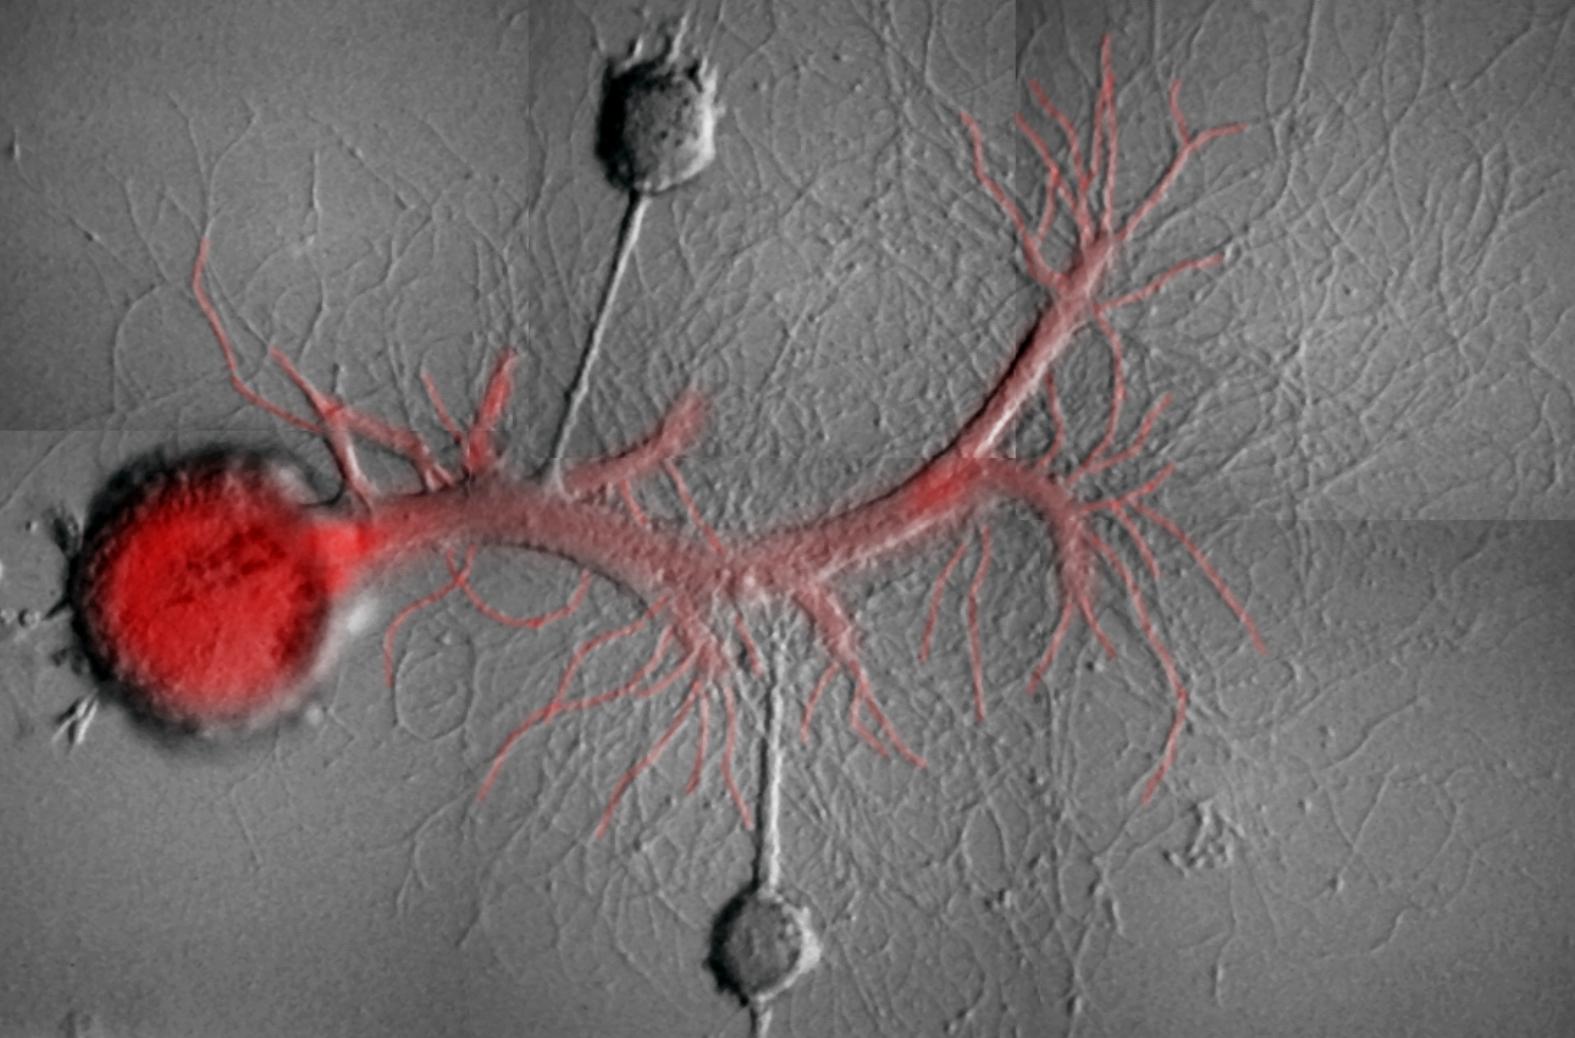

In questo studio, pubblicato su Current Biology, i ricercatori della McGill University e della Columbia hanno cancellato selettivamente un certo tipo di ricordi sinaptici a lungo termine da una lumaca marina chiamata Aplysia. I team hanno rilevato che la forza delle memorie associative e non associative viene mantenuta da due diversi tipi di proteina Chinasi M (PKM,) bloccando una di queste molecole si può decidere quale memoria eliminare.

“Guardando ai circuiti neurali, in particolare, individuare l’identità di cellule specifiche che codificano una memoria non è così semplice, senza tenere conto dell’analisi della modifica della forza di trasmissione sinaptica,” ha scritto Schacher. “Quindi, in questo studio, siamo riusciti a invertire i cambiamenti a lungo termine della forza sinaptica delle sinapsi note per contribuire a diverse forme di ricordi che si conservano per varie settimane.”